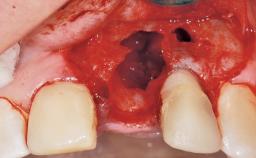

Late Flapless Placement of an Implant in a Maxillary Left Central Incisor Site

A 39-year-old male patient presented with a chief complaint of discomfort and gingival discoloration around his maxillary left central incisor. He was in good general health and was a non-smoker. His past dental history was significant because of the traumatic fracture of tooth 21 in a sporting accident at age 13. Initial dental treatment included endodontic therapy and a full-coverage restoration. The patient became symptomatic 5 years later, when structural failure of the tooth resulted in the dislodgment of the crown. Endodontic retreatment, apical surgery, and post-and-core restoration were performed.

Soft Tissue Anatomy Intact Defective

Bone Volume Horizontally and vertically sufficient Horizontally deficient Deficient vertically or deficient vertically AND horizontally

Soft Tissue Grafting Simultaneous